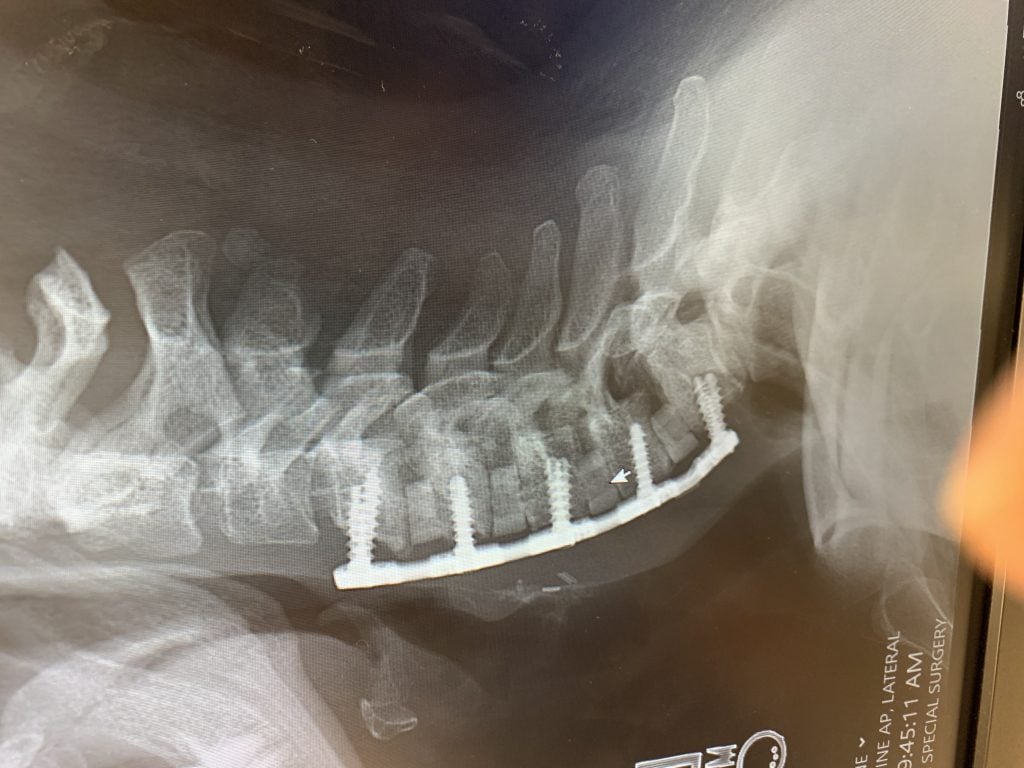

In my cervical spine I had 4 levels of compressed nerves, C-4-T1, spondylolisthesis, spondylolysis, spinal stenosis and severe degenerative disc disease. I was only 42 years old. I saw 2 local surgeons in Albany who both said surgery was imminent. However, one said he would go through the front of my neck (anterior), while the other said he did not think an anterior cervical fusion would hold because of the severe structural compromise of my neck. He said he would go in through the back (a very painful recovery with longer healing time).

I called him panicking on Monday. He took the call and calmed me down. Right before the surgery he came to talk to me and told me "Positive Energy." This man changed my life. It was an 8 hour surgery through the front. He did It! He visited me afterwards and told me what he did. He said it went great. I had to wear a brace for 10 weeks, but it was not bad. I had my 3 month follow up yesterday and got many clearances! No shoveling still though. HAHA guess my husband will have to do that.